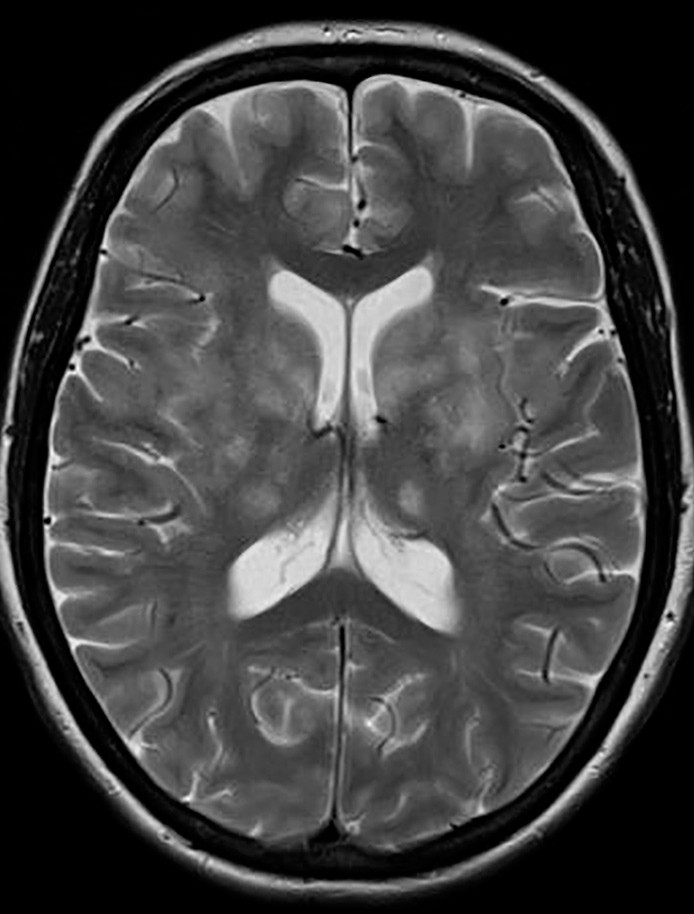

Pasienten fikk andre rituximabdose og startet med prednisolon 30 mg daglig. En måned etter behandling kunne hun gå med støtte, hadde lett dysartri og apraksi. Hennes kliniske tilstand ble stadig bedre. MR caput utført to måneder etter andre rituximabinfusjon viste nærmest fullstendig tilbakegang av områdene med økt T2-signalintensitet i hvit substans rundt sideventrikler og i basalganglier.

Som nevnt finnes det ikke spesifikke diagnostiske prøver for Behçets sykdom. Diagnosen må derfor stilles på bakgrunn av kliniske manifestasjoner der slimhinneulcerasjoner forekommer hos samtlige pasienter (5, 15). Hos ca. 60 – 70 % av tyrkiske og japanske pasienter med sykdommen finner man positiv HLA-B51 i serum (18,19). Prøven er positiv hos bare 10 – 25 % av europeiske pasienter. Spinalvæskeundersøkelse avdekker forhøyede proteiner og pleocytose, isoelektrisk fokusering er ofte negativ (5). Det er også rapportert om pasienter med kun forhøyet totalproteinnivå i spinalvæsken (11). Patergitest viser papulopustulært erytem 24 – 48 timer etter intrakutant stikk med en steril 21G-nål på underarmen. Denne testen er positiv hos halvparten av pasientene fra endemiske områder, men bare 10 – 20 % av pasientene fra Nord-Europa får positive funn ved patergitest (20). Ved den parenkymatøse formen av nevrologisk Behçets sykdom viser MR caput med T2-vektede bilder typisk hyperintense lesjoner i hjernestammen, spesielt mesencephalon, og i basalganglier (5, 14). Forandringer i hvit substans subkortikalt, frontalt og temporalt kan også forekomme (5). Lesjonene er ofte kontrastoppladende (14, 21).